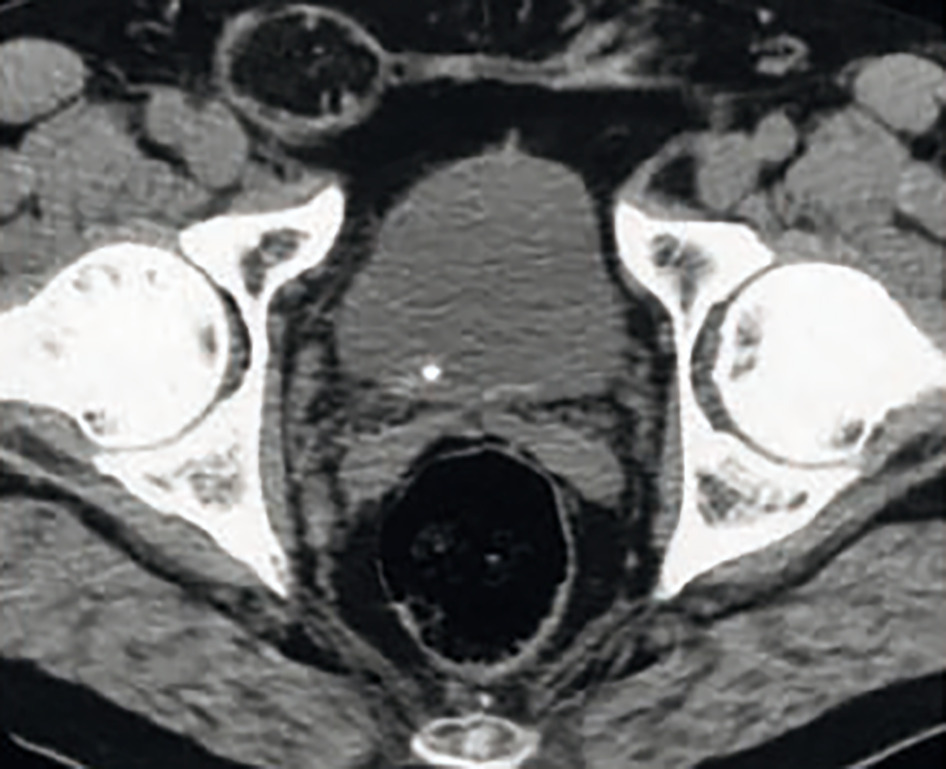

Scanner sans injection : très performant

Scanner non injecté : sensibilité et spécificité comprises entre 96 et 100 %. Examen de référence avant traitement urologique (morphologie des voies urinaires, caractéristiques et localisation du calcul).